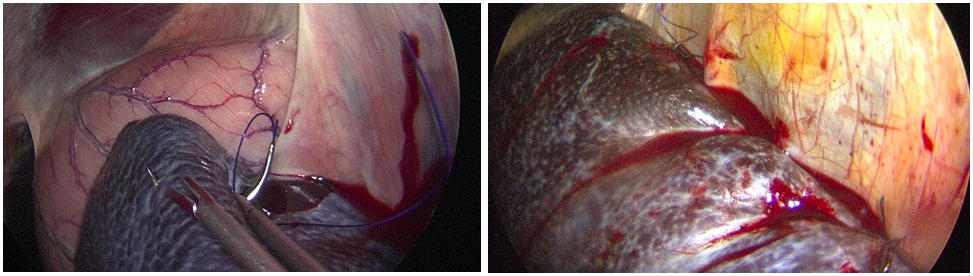

L’intervention est effectuée sur cheval debout sous sédation. Deux canules classiques et une grosse canule de 25 mm de diamètre sont utilisées. Une suture continue est réalisée permettant de juxtaposer la rate et le fascia péri rénal sous contrôle de la caméra.